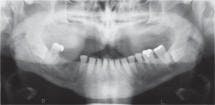

About a year ago, something happened that changed my mind. I had referred a new patient to an oral surgeon, requesting an evaluation for the removal of impacted mandibular third molars. When the oral surgeon took an extraoral panoramic film, he discovered a significant radiolucent lesion, a 2.5 cm odontogenic keratocyst involving the ramus. It had been there for a long time, but the intraoral radiographic exams that had been performed in the past had missed it.

Recently, I performed an exam on a new patient and discovered a large cyst. It obviously had been there for a long time, but could not be clearly visualized with routine intraoral X-rays. Removing this lesion will require extensive surgery. Had it been detected sooner, treatment would be far less traumatic to the patient.

In this case, the cyst looked benign. The pathology report will determine the actual diagnosis. The possibility exists, of course, that a future patient could present with a malignant lesion. Detecting an aggressive tumor early could save a patient's life. Detecting calcifications of the carotid artery could also help a patient avert an impending stroke.